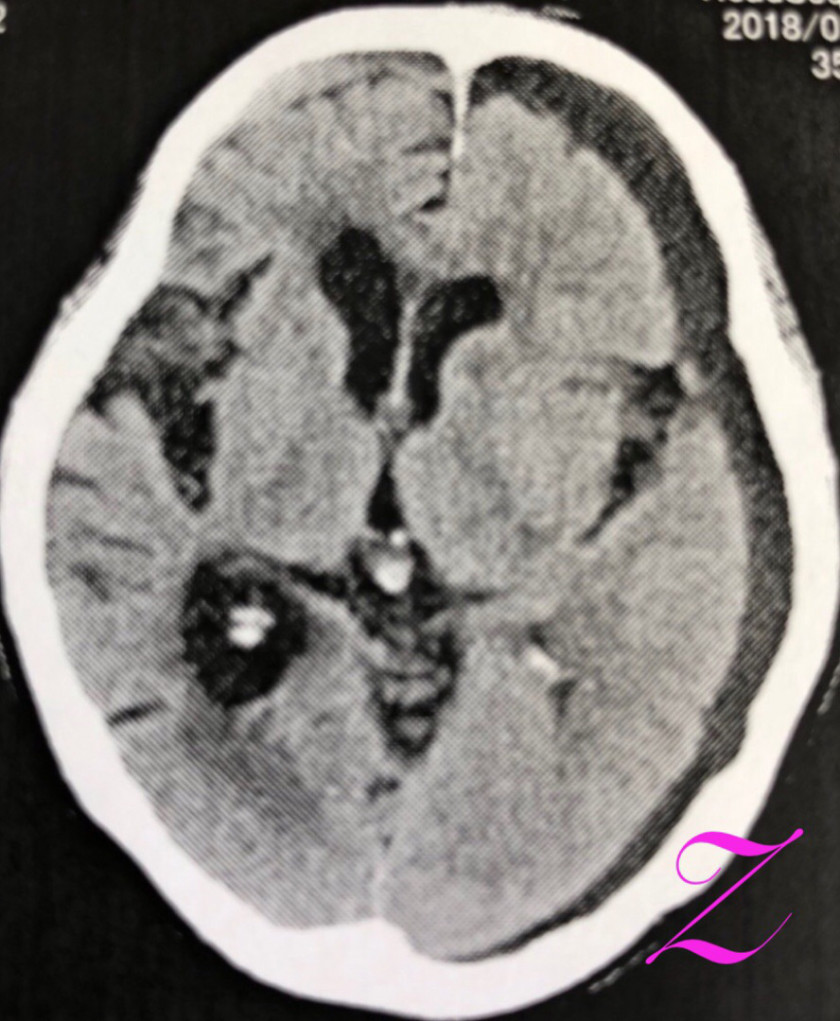

2018/06/05 急に歩けなくなったアルツハイマー症例

改訂長谷川式 11/30 遅延再生 0/6 頭部MRI(受診時)前頭葉と両側海馬の萎縮 錐体外路兆候及び行動異常 認めず。今年、3月初めに転倒。頭部CT上、血腫認めず。4月中旬、代診だったが、トイレに歩いて行けている、夜間に家の中を歩き回って困る等、歩行障害はなかった。5月中旬、「歩けなくなった」と受診。見当はついているので、脳外科を紹介。その返事に同封されていた写真が上のもの。無事にオペも終わり、元気であると、わざわざ、御家族が御礼の挨拶に来院され、近況を聞くことができた。でも、両側に血腫があるとは思っていませんでした。

80歳代 女性。昨年末から診療開始。改訂長谷川式 11/30 遅延再生 0/6 頭部MRI(受診時)前頭葉と両側海馬の萎縮 錐体外路兆候及び行動異常 認めず。今年、3月初めに転倒。頭部CT上、血腫認めず。4月中旬、代診だったが、トイレに歩いて行けている、夜間に家の中を歩き回って困る等、歩行障害はなかった。5月中旬、「歩けなくなった」と受診。見当はついているので、脳外科を紹介。その返事に同封されていた写真が上のもの。無事にオペも終わり、元気であると、わざわざ、御家族が御礼の挨拶に来院され、近況を聞くことができた。でも、両側に血腫があるとは思っていませんでした。